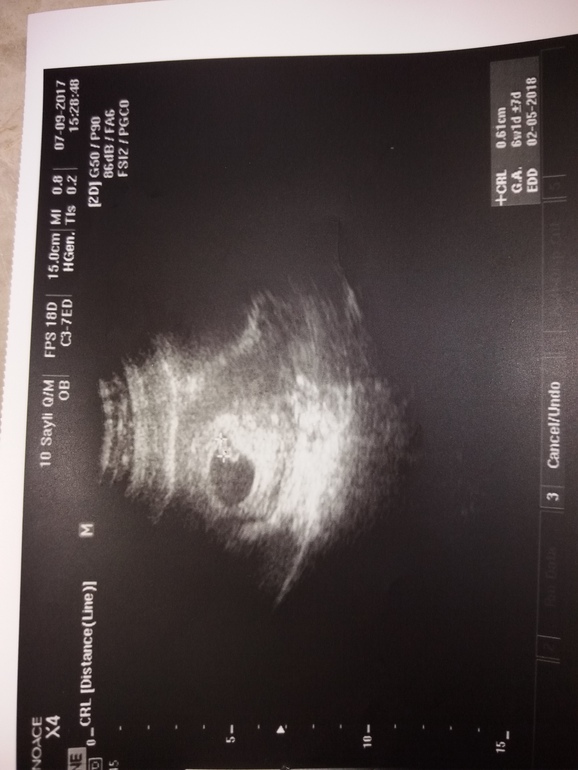

Первое узи

ну вот наконец-то!сегодня сходили мы на узи.

нам 6неделик 1день😊у нас уже бьетса сердечко💖🤗❤😇